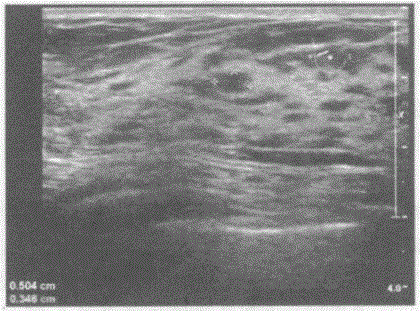

问题 临床资料:女,35岁,自述双侧乳房轻度胀痛,以月经前期明显,月经来潮后疼痛减轻。 超声综合描述:双乳腺腺体层厚度1.6cm,回声不均,结构紊乱,可见大小不等形态各异的小无回声区,部分融合。 超声提示:

选项 A.乳腺正常声像图 B.双乳腺炎 C.双乳腺多发囊肿 D.双乳腺囊性增生病合并乳腺导管扩张

答案 D